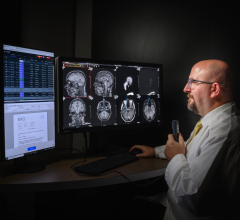

The IMPAX MA3000 Diagnostic Station is DICOM compliant and supports rapid and simultaneous display of multimodality images. It incorporates a data management system that automatically routes relevant data (e.g., DR mammography, breast MRI, ultrasound) based on a variety of user-definable criteria including modality, patient and referring physician. Relevant prior exams can be pre-fetched from the archive management system and sent automatically to the IMPAX MA3000 station. Radiology results from the RIS can be displayed simultaneously when available. Review and comparison of images can be defined per user and per modality.